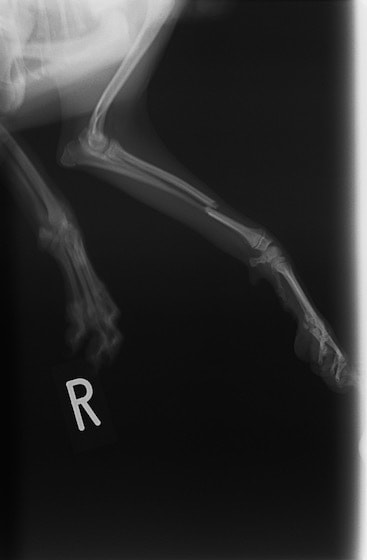

トイプードル 右遠位橈尺骨短斜骨折のALPSによる内固定